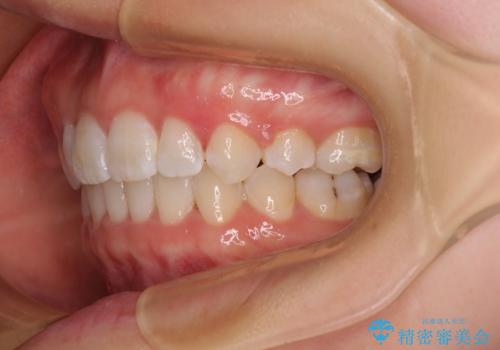

- 上下前歯のデコボコを気にして来院された患者様です。

口元の突出感はあまりなかったものの、デコボコを非抜歯で改善すると出っ歯になる可能性があるため、上下左右の第一小臼歯4本を抜歯し、ワイヤー装置にて矯正治療を行うこととしました。

口元の突出感がない分、奥歯を前方に移動させる必要がありましたが、予定の2年間で無事に治療を終えることができました。